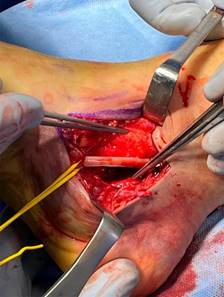

Se decidió intervención quirúrgica urgente. Ante la alta sospecha de interposición de partes blandas por el pliegue cutáneo existente, se realizó un abordaje paralelo a la planta del pie entre el maléolo medial y la cabeza del astrágalo (Figura 5), apreciándose una interposición de paquete neurovascular tibial posterior alrededor del cuello del astrágalo (Figura 6). El nervio tibial posterior mostraba signos de contusión, mientras que la arteria y vena se encontraron íntegras, pero con signos de sufrimiento.

Figura 5: Incisión quirúrgica medial entre cabeza del astrágalo y maléolo medial, paralela a la planta del pie.

Figura 6: Imagen intraoperatoria en la que se muestra la interposición del paquete neurovascular tibial posterior alrededor del cuello del astrágalo.